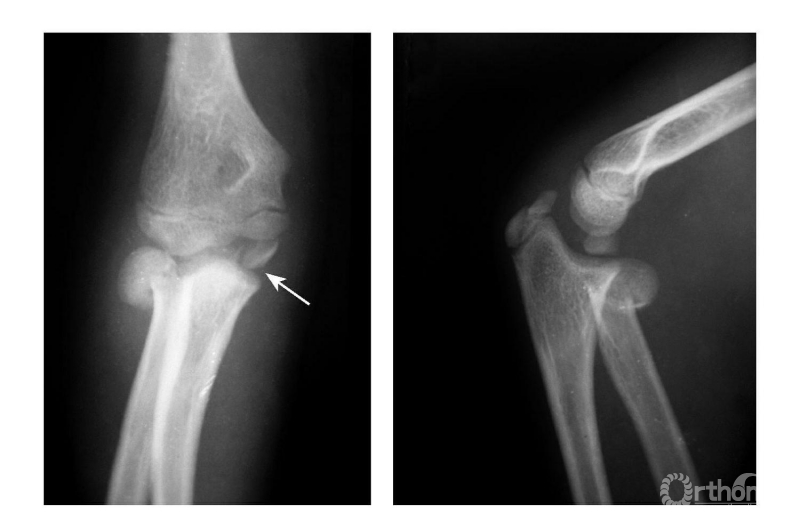

Ⅳ度损伤:

例1:肘关节外后脱位并肱骨内上髁撕脱骨折,骨块移向尺肱关节间(图9)。

图9

例2:肱骨内上髁Ⅳ度骨折并肘关节旋转性脱位(图10)。

图10